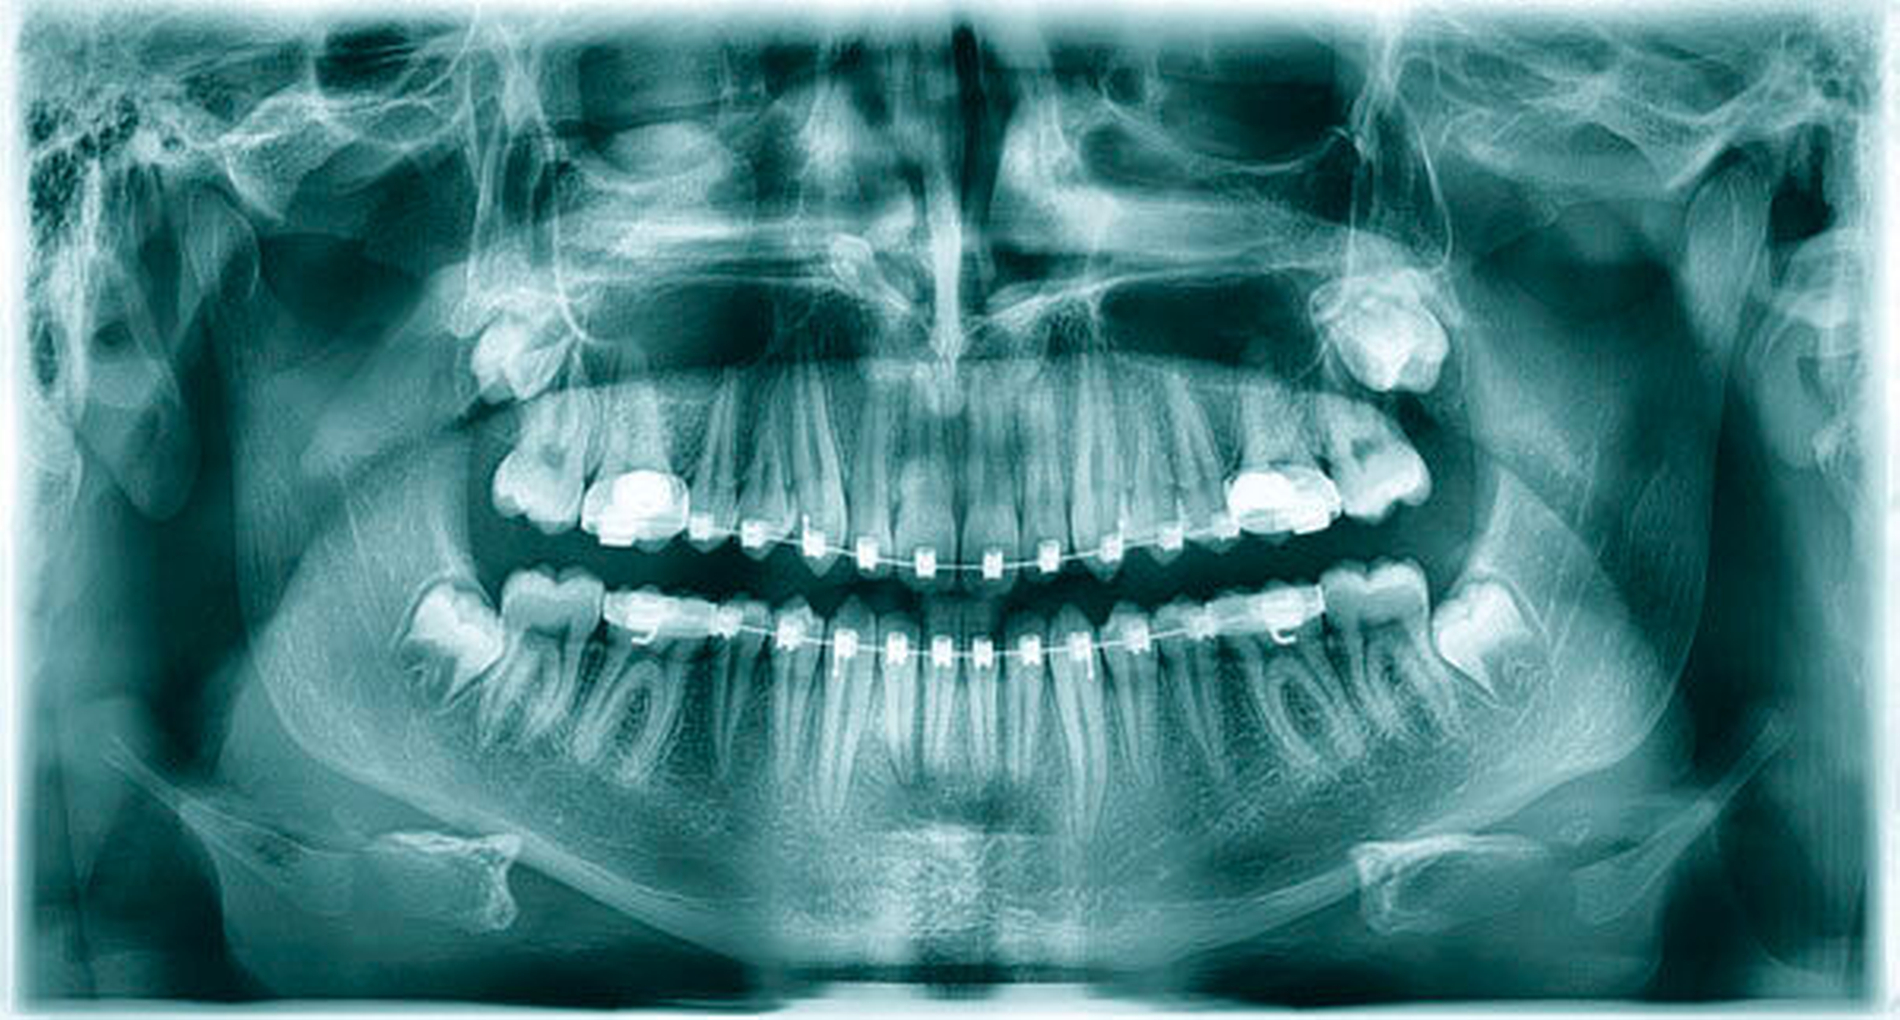

Das angefertigte OPT (Abbildung 1) zeigte einen ektopen, überzähligen Zahn 13a. Nach Komplettierung der Bildgebung durch eine Computertomografie (Abbildungen 2a und 2b) fand sich der Zahn kranial im rechten Nasenboden gelegen. Nebenbefundlich konnte eine polypöse Schleimhautschwellung der rechten Kieferhöhle festgestellt werden.